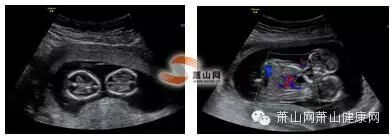

无独有偶,同年8月,怀孕13周的徐女士到浙江萧山医院行早孕NT超声筛查时被确诊为联体双活胎。屏幕显示,这两个小宝宝相拥着躺在妈妈的肚子里,胸腹部紧密相连,却只有一个肝脏和心脏,彼此温暖着、感受着同样的心跳,还时不时互相碰头“打招呼”,乍一看就像在抱着亲亲。场景虽是有爱,但却让人直叹惋惜。